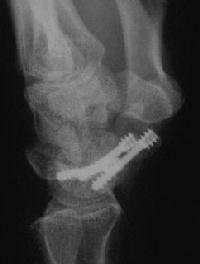

Case 2. Nonunion with a large fracture cyst. After debridement, the defect, the graft, and yes, that is the capitate peeking through the defect.

Click for larger image

The graft, and inadequate seating of the more ulnar screw.